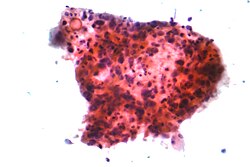

Karcinomi pluća se klasificiraju prema histološkom tipu.[8] Ova klasifikacija je važna za određivanje liječenja i prognozu ishoda bolesti. Većina zloćudnih tumora pluća su karcinomi, zloćudni tumori koji potječu od epitelnih stanica. Karcinomi pluća se svrstavaju na osnovi izgleda zloćudnih stanica koje određuje patolog, pomoću mikroskopa. Dvije najšire skupine su ne-sitnostanični i sitnostanični karcinomi pluća.[44]

Tri glavna podtipa ne-sitnostaničnog karcinoma pluća su adenokarcinom, karcinom pločastih stanica i velikostanični karcinom.[1]

Oko 40% karcinoma pluća su adenokarcinomi, koji se obično počinju razvijati na periferiji pluća.[8] Većina adenokarcinoma je povezana s pušenjem, međutim u osoba koje su u životu popušile manje od 100 cigareta (što se računa kao da nisu nikada pušile),[1] adenokarcinom je najčešći oblik karcinoma pluća.[45] Podtip adenokarcinoma, bronhioloalveolarni karcinom, je učestaliji u žena koje nikada nisu pušile i može imati bolju dugoročnu prognozu.[46]

Karcinom pločastih stanica (planocelularni karcinom) čini oko 30% svih karcinoma pluća. On se tipično razvija u velikim bronhima. U središtu ovog tumora često se nalazi šupljina uslijed nekroze tumorskih stanica.[8]Oko 9% karcinoma pluća su velikostanični karcinomi, koji se nazivaju tako jer su tumorske stanice izrazito velike, s obilnom citoplazmom, velikim jezgrama i uočljivim nukleolima.[8]